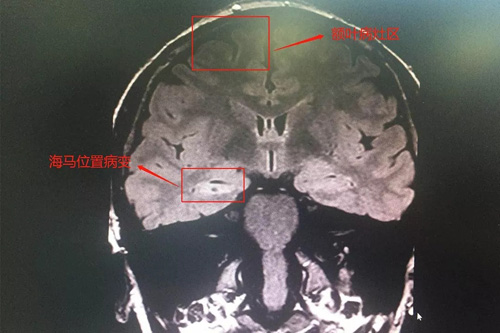

为了防止监测过程中再次病发影响监测,医生给我注射了镇静剂。经过24小时不间断观察,终于明确了病因,崔主任介绍,我的病是一个非常典型的精神运动型癫痫,病灶位于右侧海马和额叶位置,有效的治疗手段只有手术切除。切除了癫痫病灶,才能摆脱反复的折磨。